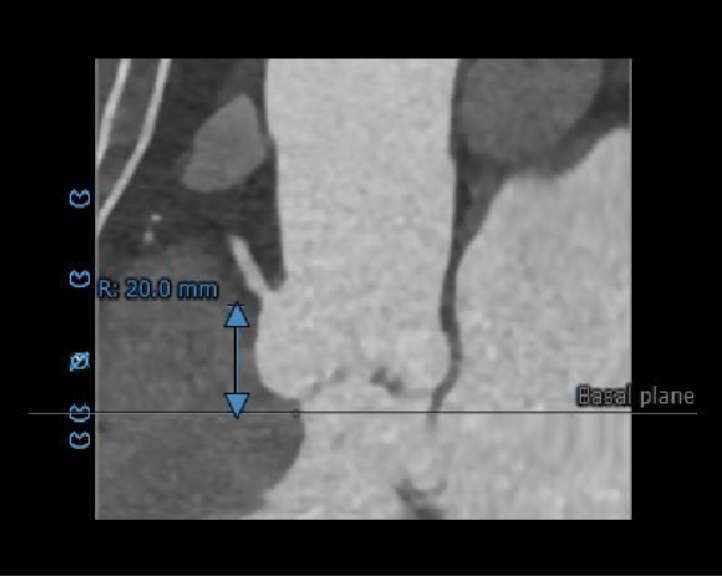

冠脉高度测量

左冠开口高度15.5mm

右冠开口高度20.0mm